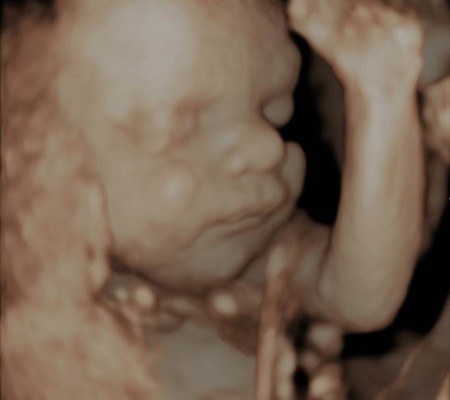

3D i 4D tehnologija omogućava da vidimo površinu bebe na lepši način i pokrete ploda u realnom vremenu.

Takođe nam omogućava da bolje vidimo fetalne mane na licu, šakama i stopalima.

Kao i 2D, 3D i 4D koriste ultrazvučni talas da se kreira slika bebe u materici. 3D je kreirana slika u prostoru dok 4D prikazuje pokret unutar materice pa možemo videti kako se beba smeje, mršti ili zeva.

Da bi se dobile dobre slike poželjno je da se pregled radi između 24 i 32 nedelje trudnoće.